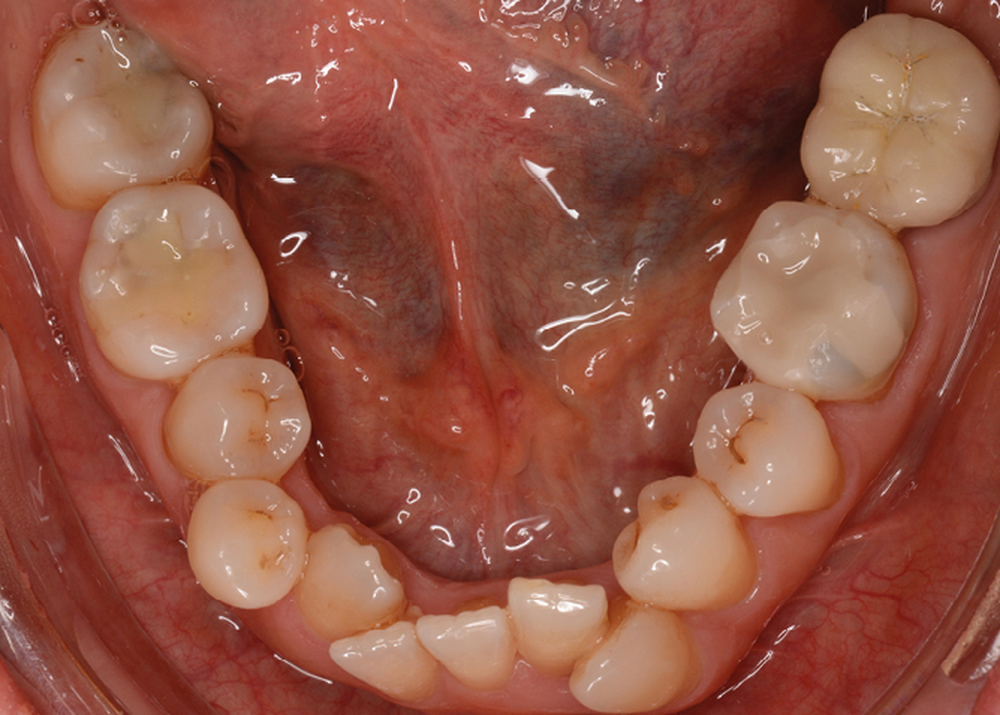

Sur le plan dentaire, la patiente est en classe III droite et gauche, canine et molaire de 6 mm, avec une occlusion inversée antérieure localisée à 11, 12 et 22. Elle présente une dysharmonie dents-arcades sévère, une agénésie d’une incisive mandibulaire est à signaler, et les troisièmes molaires ont été extraites à l’âge de 21 ans.

Au niveau fonctionnel, on note un bruxisme statique avec contact permanent entre les dents maxillaires et mandibulaires. La patiente présente des prématurités en relation centrée sur les incisives, le guidage en propulsion est perturbé et des interférences multiples sont retrouvées en latéralités droite et gauche.